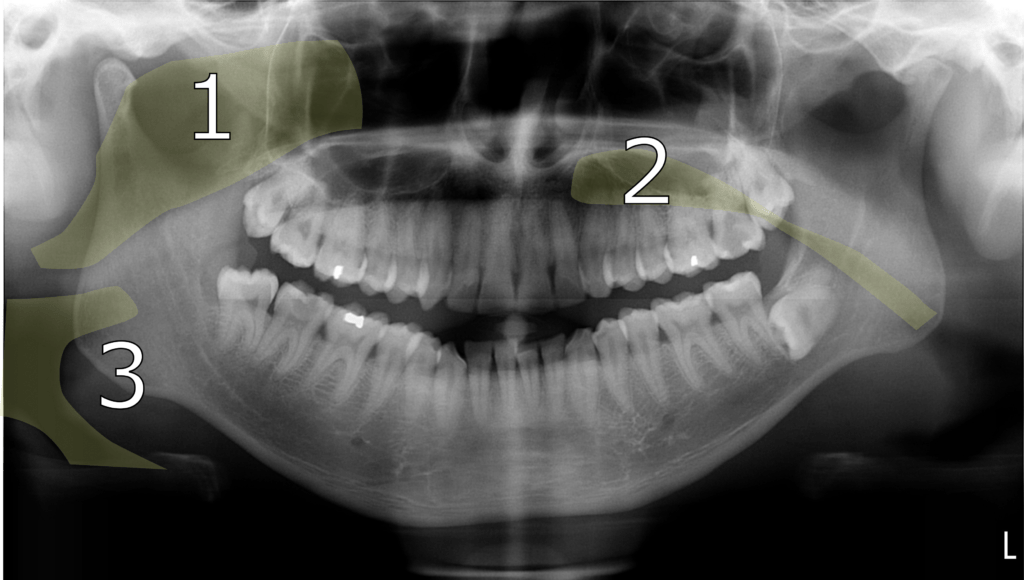

The orthopantomogram (aka orthopantomograph, pantomogram, OPG or OPT) is a panoramic single image radiograph of the mandible, maxilla and dentition. The image is a three-dimensional curved focal trough flattened out to a two-dimensional image. Structures lying within the focal trough are well-defined and in focus. Structures outside the focal trough are blurred, magnified, and sometimes distorted. The patient remains seated or standing while both the x-ray source and the film rotate around the patient’s head. The x-ray source rotates in front of the patient, the film rotates opposite to the x-ray source behind the patient. It takes a few seconds during which the patient must remain completely still. Orthopantomograms are most commonly used in dental practice and occasionally in the emergency department. The OPG is used to:

- Evaluate general dental health & development.

- Screen for caries, pulpal pathology, impaction etc.

- Assess jaw trauma or pathology.

- Review infection or inflammation (sinusitis, periodontitis, periapical abscesses etc.).

- Evaluated tumors or cysts.

- Assess temporomandibular joints for disease, fractures or dislocations.

- Localize foreign bodies.

- Identify salivary stones (sialolithiasis).

- Monitor growth and development.